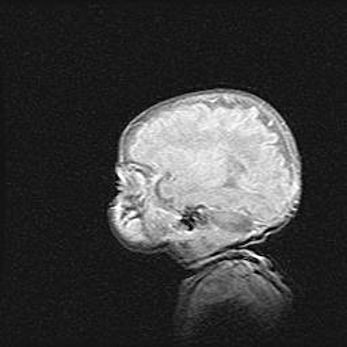

Церебральная ишемия II.

Возраст: 5 дней

Вес: 3400 г

Пол: женский

Окружность головы: 35 см

Срок гестации: 39 недель

Церебральная ишемия – это заболевание, характеризующееся недостаточностью (гипоксией) либо полным прекращением (аноксией) снабжения мозга кислородом по причине закупорки одного или нескольких сосудов. Это приводит к  что метаболическим расстройствам различной степени тяжести в тканях головного мозга, развитию коагуляционных некрозов и гибели нейронов.